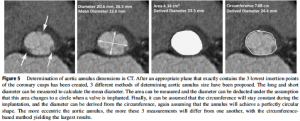

3. MSCT

Multislice computer tomogoraphy (MSCT)はSHDインターベンションにおいて正確な解剖学的/幾何学的情報を得ることができるModalityである。特にTAVRにおいては、デバイスの選択や石灰化に伴うリスク評価のgold standardとなっている(5,6)。アクセスルートの適切な選択のための血管評価、冠動脈形態評価、手技時の適切なX線照射角度、肺野の評価などを同時に行える点もメリットが大きい。また、石灰化スコアを用いた弁膜症重症度評価も特にLow-flow Low-gradient ASについて有用であると報告されており広く用いられている(7,8)。

(文献5より引用: CTによるTAVR術前のLVOT評価)

(文献5より引用: CTによるTAVR術前のLVOT評価)

しかしながら放射線被曝と造影剤投与が必要になる点はMSCTの大きな弱点である。簡便さ/非侵襲性に関してはエコーに及ばない。また、不整脈、頻脈による画質の低下を防ぐためにβ遮断薬の使用が必要であることも留意すべき点である。